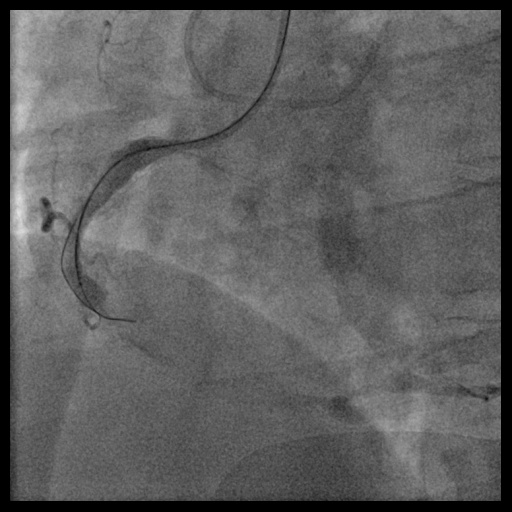

In 2020, he was admitted for NSTEMI. Emergency coronary angiography showed total occlusion of the right coronary artery (RCA). Initial attempts with a Fielder FC wire failed. Using a Gaia 1 and then Gaia 2 wire with a Progreat microcatheter, the lesion was successfully crossed. Predilatation was done with Euphora balloons (2.0 × 20 mm, 3.0 × 30 mm). Two Xience Sierra stents (3.5 × 38 mm, 3.5 × 15 mm) were deployed, followed by post-dilation with Accuforce balloons (4.0 × 20 mm, 4.5 × 15 mm).

Relevant Catheterization Findings

During this emergency catheterization, the right radial artery was accessed using a 20-gauge needle. A 6 Fr in 5 Glidesheath Slender® (Terumo Corp., Tokyo, Japan) was inserted. Coronary angiography was performed using Terumo 5 Fr Judkins catheters, revealing in-stent total occlusion of the RCA and patent left coronary artery (LCA).

In anticipation of a high thrombus burden, intracoronary Tirofiban was given to mitigate thrombotic risks. The Terumo 6 Fr in 5 Glidesheath Slender was exchanged for a 7 Fr in 6 Glidesheath Slender to accommodate larger catheters while preserving radial artery access. Using a 7 Fr SAL 1.0 guiding catheter (Medtronic, USA), the Fielder FC 0.014” × 180 cm wire (ASAHI Intecc, Japan) was advanced to the distal RCA. Despite GuideLiner (Teleflex, USA) support, the Terumo Eliminate aspiration catheter could not advance beyond the mid-RCA. StentBoost imaging revealed the wire had wound along the aneurysmal vessel wall and passing through a previous stent’s strut. Attempts to reshape the wire tip for re-entry into the stent center were unsuccessful. Although stent crushing was considered, navigating the wire through the stent without damage was prioritized. An Euphora balloon (2.0 × 20 mm) was inflated at 2 atm to seal the gap between the stent and vessel wall, enabling the passage of a Runthrough NS Floppy wire into the distal RCA. IVUS confirmed the wire’s position within the stent, which remained intact. The wire was exchanged for an ASAHI Sion Blue Extra-support wire with a Caravel microcatheter. Thrombus aspiration was completed using the Eliminate catheter. Post-dilatation was performed with a Conqueror NC balloon (4.00 × 20 mm, APT Medical), followed by NC Emerge and Accuforce balloons (4.5-6.0 mm). IVUS confirmed excellent stent apposition, and TIMI 3 flow was achieved.